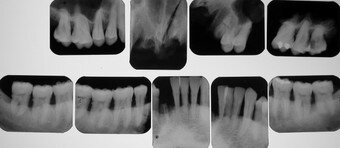

There is something I don't understand. His Wiki says that his teeth were removed, but Namus says his dental information is available and entered. There are even dental radiographs available on his Namus page, so I suppose his Wiki page has some false information.